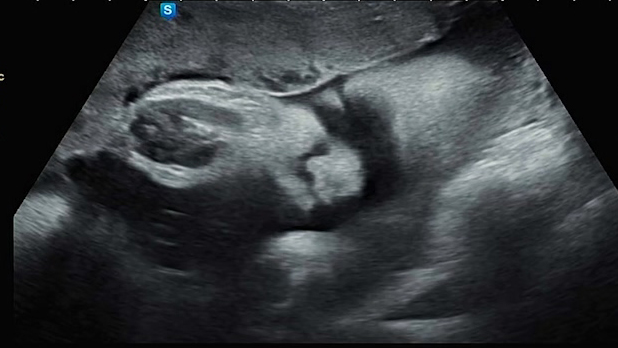

영상 첫순간부터 포동한 까꿍이의 얼굴 등장! 마지막 초음파 검사라는 것을 알았는지 까꿍이가 서비스로 얼굴을 많이 보여줘서 좋았다. 손도 다행히 안 가리고 있었음😍😘

아는 사람한테만 보인다는 초음파 사진. 대략적인 실루엣으로 표현되는 눈, 코, 입이다. 아무래도 초음파는 굴곡을 층별로 표현하기 때문에 이목구비가 잘 표현되는 단면도에서는 저렇게 코와 입술이 굉장히 두툼해 보인다. 눈 기준으로 깊이감을 조절하다 보니 그러는 것 같았다.

아내가 원장님 말로는 살짝 눈 뜨고 있는 것 같다고 하셨다고 했다. 약간 갓난아기 얼굴 느낌이 나오기도 하고,,,아내가 체중 적을까 봐 꾸준히 잘 챙겨 먹었는데 포동포동 건강하게 잘 크고 있는 것 같아 보기 좋았다 :)